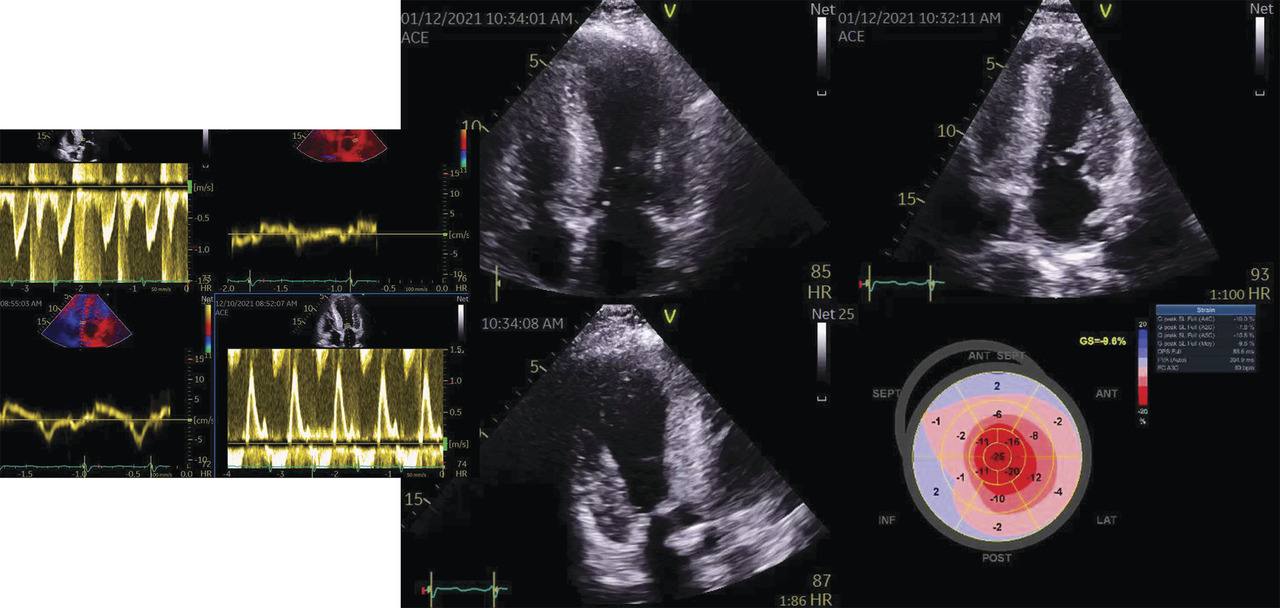

Le cas particulier de l’amylose à transthyrétine

Il existe aussi des formes particulières d’ICFEP et en particulier celle de l’amylose à transthyrétine (TTR) qui est retrouvée dans 13 % des cas de patients ayant une ICFEP. Son diag­nostic est important car un traitement spécifique est possible. Il faut rechercher un strain en cocarde (fig. 4) et s’aider de la fixation assez spécifique du massif cardiaque lors d’une scintigraphie osseuse (où normalement le massif cardiaque ne fixe pas).36, 37